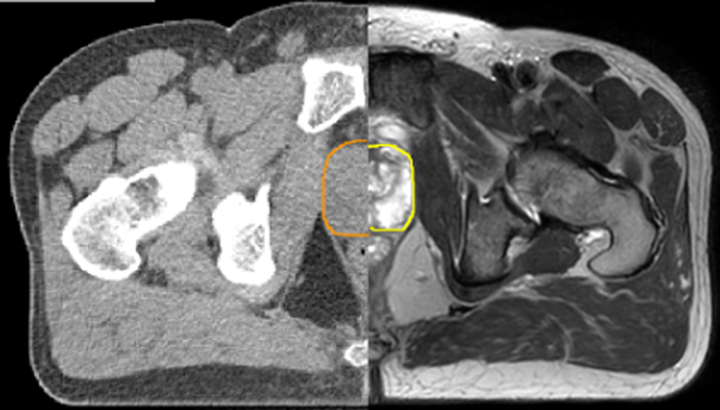

With its superior soft tissue contrast compared to CT, MRI offers exquisite visualization of tumor boundaries and proximity to nearby critical structures.

The ability to tune contrasts can provide even more valuable information about tumor characteristics and tumor extent to facilitate enhanced delineation, and also provides possibilities for dose boosting strategies.